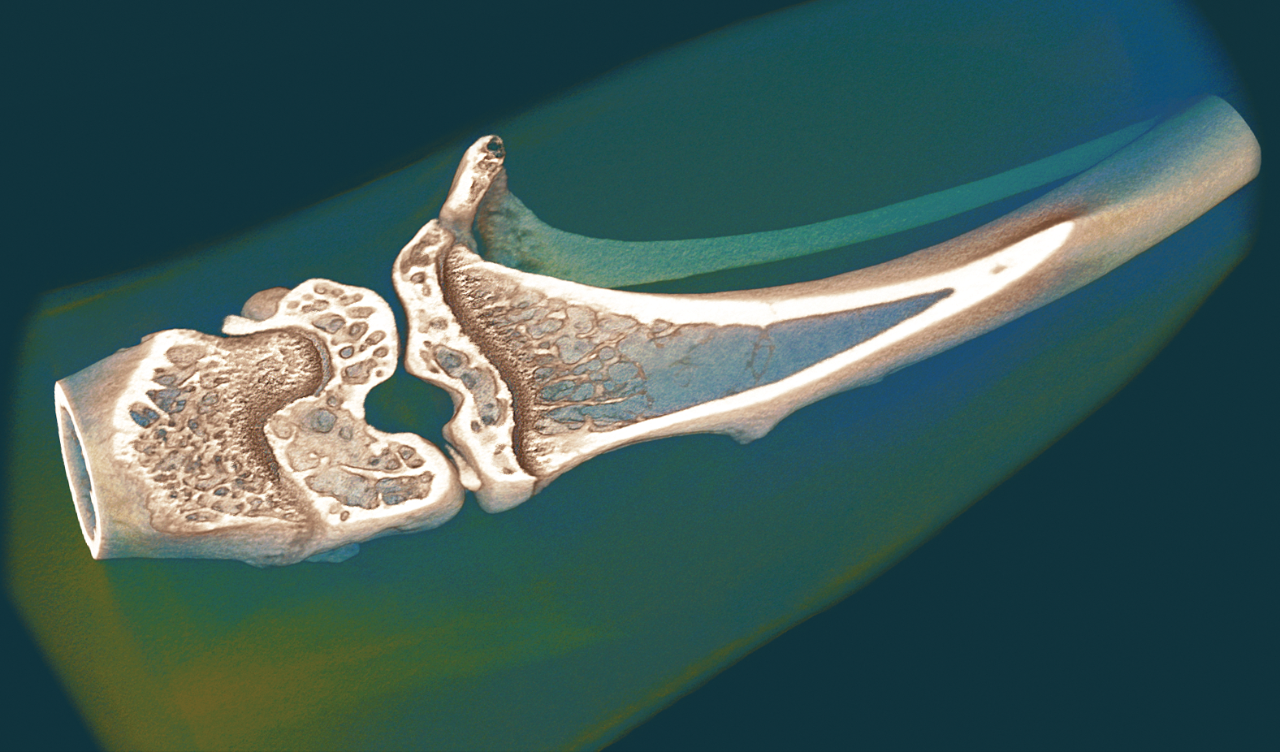

1. Volume rendered 3D model of a femur with color-codedrepresentation of the trabecular thickness, scanned at 2.8 umpixel size